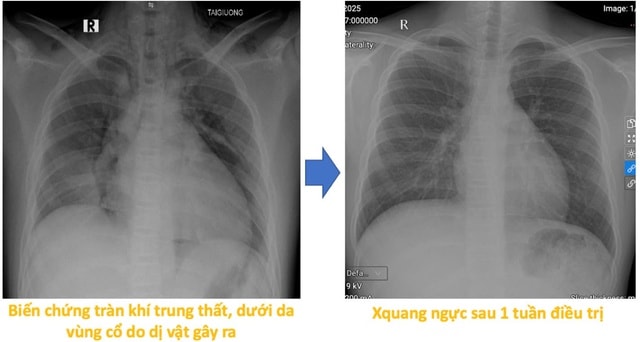

Sau thủ thuật, bệnh nhi giảm ho nhiều, đỡ khó thở và còn tức ngực nhẹ, song vẫn phải theo dõi do có biến chứng tràn khí trung thất và tràn khí dưới da vùng cổ. Hiện tại sức khỏe của bệnh nhi đã ổn định, các triệu chứng cũng tiến triển tốt và vẫn đang được điều trị theo phác đồ nội khoa sau hít phải dị vật.